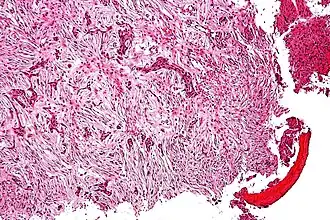

| Microfotografia de um adamantinoma. | |

Adamantinoma ósseo é um tumor maligno de baixo grau, descrito por Fischer em 1913, acometendo pessoas da segunda e terceira décadas de vida, estando em 85% dos casos presente na tíbia. Cursa com metástase pulmonar de aparecimento tardio, da ordem de 15%.[1]

Sua etiologia é ainda interrogada; estudos corroboram provavelmente com origem epitelial. O adamantinoma da mandíbula (hoje ameloblastoma) é originário da dentina, e viu-se que, apesar de parecido na histologia, é um tumor totalmente diferente do adamantinoma da tíbia.

A clínica é de dor insidiosa e massa palpável, porém 20% abrem com quadro de fratura patológica. Diferencia-se da displasia osteofibrosa por esta incidir em menores de 10 anos, ser indolor e totalmente intracortical. Na radiologia, o adamantinoma apresenta-se como múltiplas lesões líticas excêntricas acometendo grande área em diáfise da tíbia com contornos bem definidos. Inicia-se na cortical, mas invade medular. Pode ainda invadir a fíbula por contiguidade.